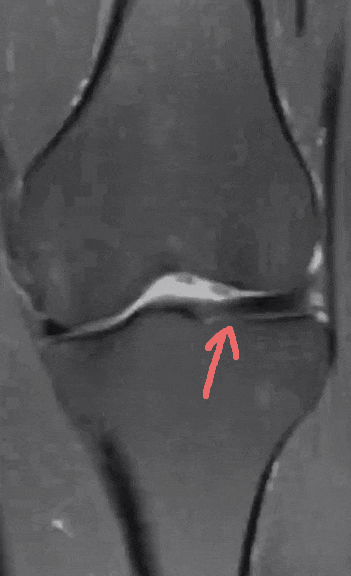

令小张一家感到惊讶的是,医生看到磁共振影像后说,小张的半月板不仅撕裂,而且还存在先天畸形——叫作「盘状半月板」。

从影像上可以看出,小张的半月板比正常人的更大更厚。

正常的半月板,类似「C」字或「O」字型。而盘状半月板,如同盘子一般又圆又厚,因此命名为盘状半月板。